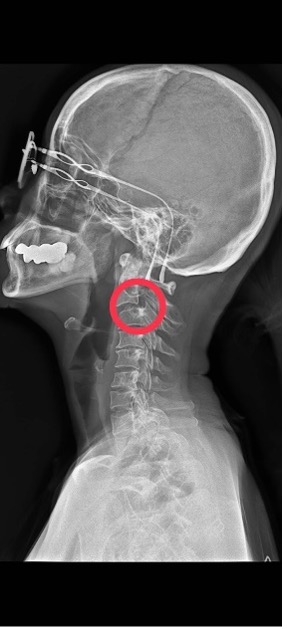

如以下X光片可見:

1 其頸椎第一節和第二節沾粘,頭部因此轉動困難,故頸椎第三節承接頭部轉動的功能,長久以來致頸椎第三節移位滑脫,未來神經一旦有阻斷即可造成癱瘓的可能。

2. 頸椎與胸椎接連處有旋轉性的傷害(未呈直線),造成肩頸肌肉組織持續扭轉傷痛。由1&2推理,本個案或可能是曾經受到嚴重外力傷害所致。

本個案頸椎呈現具極高的危險狀況,任何治療均可能造成神經傷害致癱瘓或危及生命。日常生活需要十分小心。帶防護性的頸圈或許會有幫助。